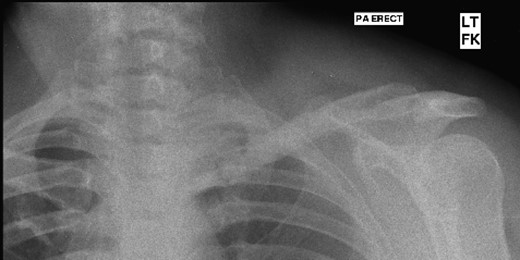

A 45-year-old woman presented with a 20-year history of a lump in the mid-third of the left clavicle, which had recently increased in size to 10 cm in diameter. Plain X-ray, computed tomography (CT) chest and clavicle, and bone scans were used to image the lesion (Figs 1–3). Radiology reported the lesion as a parosteal osteosarcoma, based on the CT appearance of tumour growing into the medulla of the mid-third of the clavicle; not usually a feature of an osteochondroma or an osteoma. Biopsies showed dense sclerotic bone, with no obvious malignant features. To confirm diagnosis complete excision of the tumour was needed, with a partial excision and scraping the lump off the surface deemed unsafe. The patient was informed that, following a total claviculectomy, a 30% functional loss (29.5% [8]) in her left shoulder power would be expected. Her active lifestyle meant this result was unacceptable, so she opted instead for excision of the tumour plus the adjacent clavicle, irradiation and reimplantation of the bone with internal fixation, despite this being relatively experimental. If successful, she would have virtually normal function. Although possible risks included infection or development of non-union, which would require further surgery or possible complete claviculectomy, it was deemed oncologically safe with a low risk of complications.

Preoperative CT scan, axial view showing the extent of the tumour.